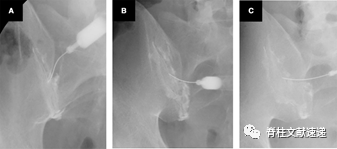

透视下骶髂关节封闭术

①   体位:患者俯卧位,疼痛一侧在透视台上,我们将后SIJ注射线分为4个等份。

②   进针点位于髂后上棘与骶骨外侧嵴边界的平行线相交点,方向几乎是垂直透视角度进针。针刺处局部麻醉,23或22号长度90.0mm的穿刺针,插入关节中间部分,也就是之前说的第2区域。

③   进针过程中遇到骨组织,此时调整透视机角度,尾倾25-30°。此时能清晰显示骶骨与髂骨之间的间隙。

④   调整针的方向至关节后缘,继续进针至髂骨壁中部,回抽,此时由于软骨的存在,有时会有堵塞感,注射造影剂时适当退回针头。然后注射造影剂充满关节腔,再注射1.5-2.0ml2%的利多卡因。

通过此技术,80%能够成功到达骶髂关节。但有文章报道了,其中80例成功的病人中有4例病人由于坐骨神经的麻醉出现短暂下肢无力,其他病人无并发症。